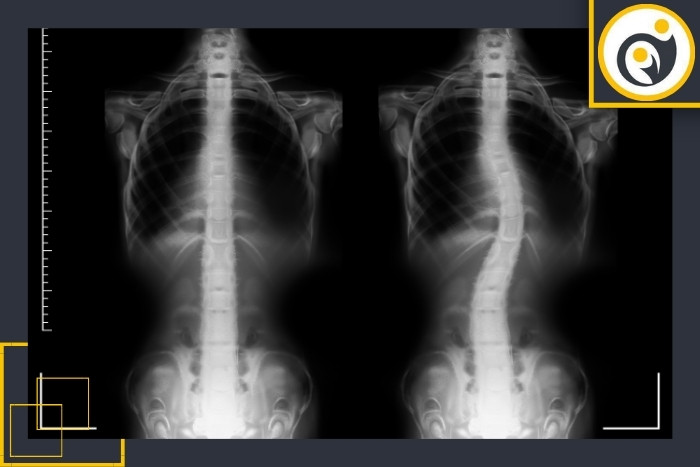

انحراف ستون فقرات یا اسکولیوز (Scoliosis) معمولاً در دوران رشد بهویژه در نوجوانان و جوانان ظاهر میشود و در صورت عدم تشخیص بهموقع ممکن است موجب درد، تغییر فرم بدن و محدودیت حرکتی گردد. شناخت علائم اولیه این عارضه به پیشگیری و درمان مؤثر آن کمک شایانی میکند. در ادامه علائم رایج این عارضه را بررسی میکنیم:

یکی از واضحترین علائم انحراف ستون فقرات نابرابری ارتفاع شانهها است. معمولاً یکی از شانهها بالاتر از دیگری قرار میگیرد. این نشانه بهویژه هنگام ایستادن یا نگاه کردن از پشت به فرد بهخوبی دیده میشود.بیرونزدگی استخوان کتف

در اسکولیوز چرخش مهرهها باعث میشود یک سمت از کتف (استخوان شانه) برجستهتر از سمت دیگر شود. این برجستگی اغلب اولین علامتی است که والدین در فرزندشان متوجه میشوند.تغییر فرم بدن و حالت ایستادن

افراد مبتلا معمولاً هنگام ایستادن یا راه رفتن بدن را کمی به یک سمت خم میکنند. ممکن است قوس غیرطبیعی در پشت یا پهلوها مشاهده شود. گاهی نیز شانه یا باسن بهصورت نامتقارن قرار میگیرد.تفاوت در طول پاها یا کج بودن لگن

در هنگام خم شدن به جلو (تست آدامز - Adams Forward Bend Test) ممکن است برآمدگی یا برجستگی در یک سمت پشت دیده شود. این نشانه یکی از مهمترین علائم برای غربالگری در مدارس و کلینیکهاست.تغییرات در وضعیت لباسها